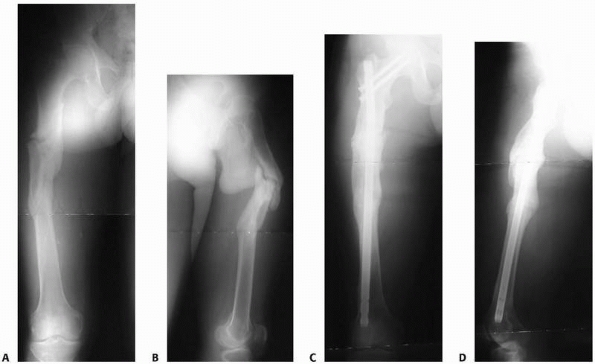

Intramedullary nail fixation is preferable when practical (Fig. 26-21).

FIGURE 26-21 A,B. AP and lateral radiographs on presentation. C,D. AP and lateral radiographs following deformity correction with closed antegrade femoral nailing.